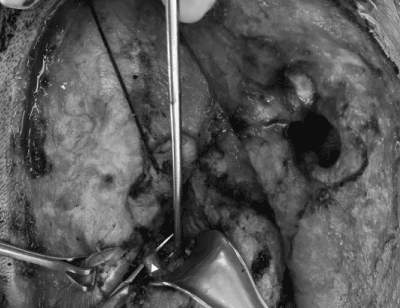

A 31-year-old female of Chinese descent was referred for evaluation of a right neck mass. This mass had been observed by her family doctor for several years and noted to be small and stable in size. However, during the third trimester of her first pregnancy, rapid growth and onset of neuropathic pain along the post-auricular skin in the greater auricular nerve distribution was noted. She had no history of head and neck radiation treatment or a personal or family history of salivary neoplasms. A firm and non-mobile mass was observed to be firmly planted between the mastoid tip and angle of the mandible. At the time of initial assessment, she was noted to have intact facial nerve function and no overlying skin changes. The remainder of her examination was unremarkable. A bedside ultrasonography examination was performed with a 12 MHz linear array probe that demonstrated a lobulated hypoechoic lesion between the mastoid tip and angle of mandible measuring 2.0 X 2.0 X 2.7 cm (Figure 1). Ultrasound-guided fine needle aspirate biopsy demonstrated cytology consistent with adenoid cystic carcinoma.

Figure 1. Ultrasound (12 MHz linear array probe) of right parotid mass demonstrating lobulated hypoechoic lesion between the mastoid tip and angle of mandible measuring 2.0 X 2.0 X 2.7 cm (volume, 5.82 cm3)